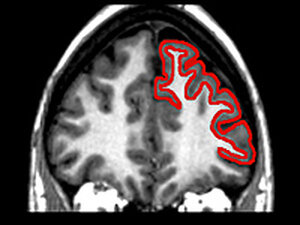

Shown in red, the frontal lobe houses the "executive system" of the brain; it decreases in volume as we age. This region helps the brain decide which tasks to focus on and when to suppress irrelevant information. Click to see a graph showing how the frontal lobe changes with aging. Raz, N et al. in Neurobiology of Aging hide caption

Shown in red, the frontal lobe houses the "executive system" of the brain; it decreases in volume as we age. This region helps the brain decide which tasks to focus on and when to suppress irrelevant information. Click to see a graph showing how the frontal lobe changes with aging.

The part of the brain that does this is called the "executive system." It's a bit like one of those cartoon conductors telling the orchestra: louder, softer, faster, slower. You come in here. You be quiet for a few measures.

The conductor in our heads lives in the brain's frontal lobes, basically above our eyes.

"Executive processes allow us to make plans for our future behaviors," Weissman said. "They allow us to exert some sort of voluntary control over our behavior."

The executive system also helps us achieve a goal by ignoring distractions.

"For example, if we're performing a task where we want to watch TV and ignore voices that are coming from, say, our children nearby," Weissman said, "our frontal region brain may configure the brain to prioritize visual information and dampen down auditory information."